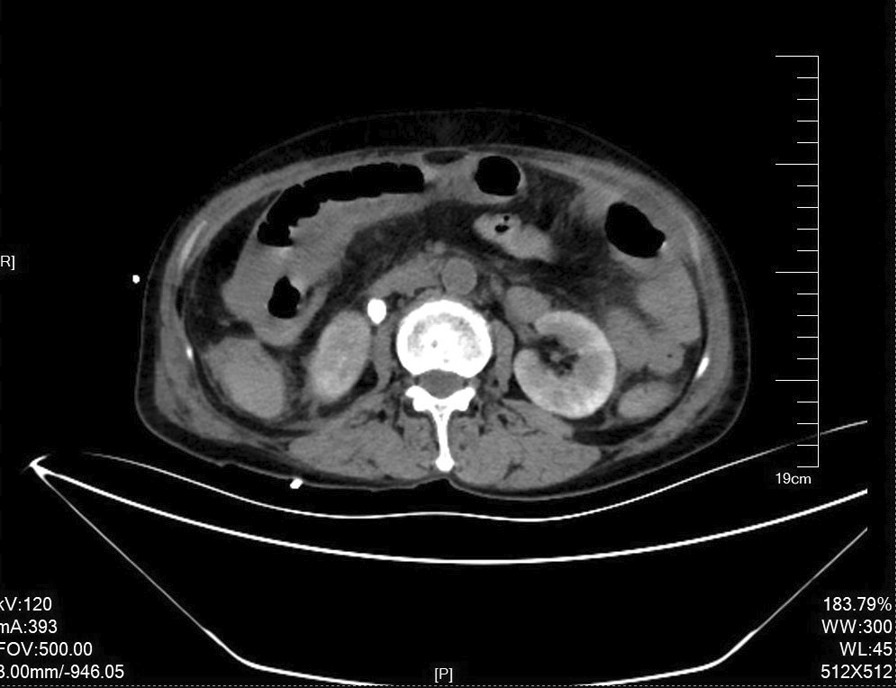

Fig. 1.

Abdominal CT-scan: intestinal dilatation, intestinal wall edema, and mesenteric exudation. Free fluid in the abdominal and pelvic cavity. Right lateral upper ureteric calculi measuring approximately 9 mm * 10 mm with right upper ureteral dilatation and hydronephrosis